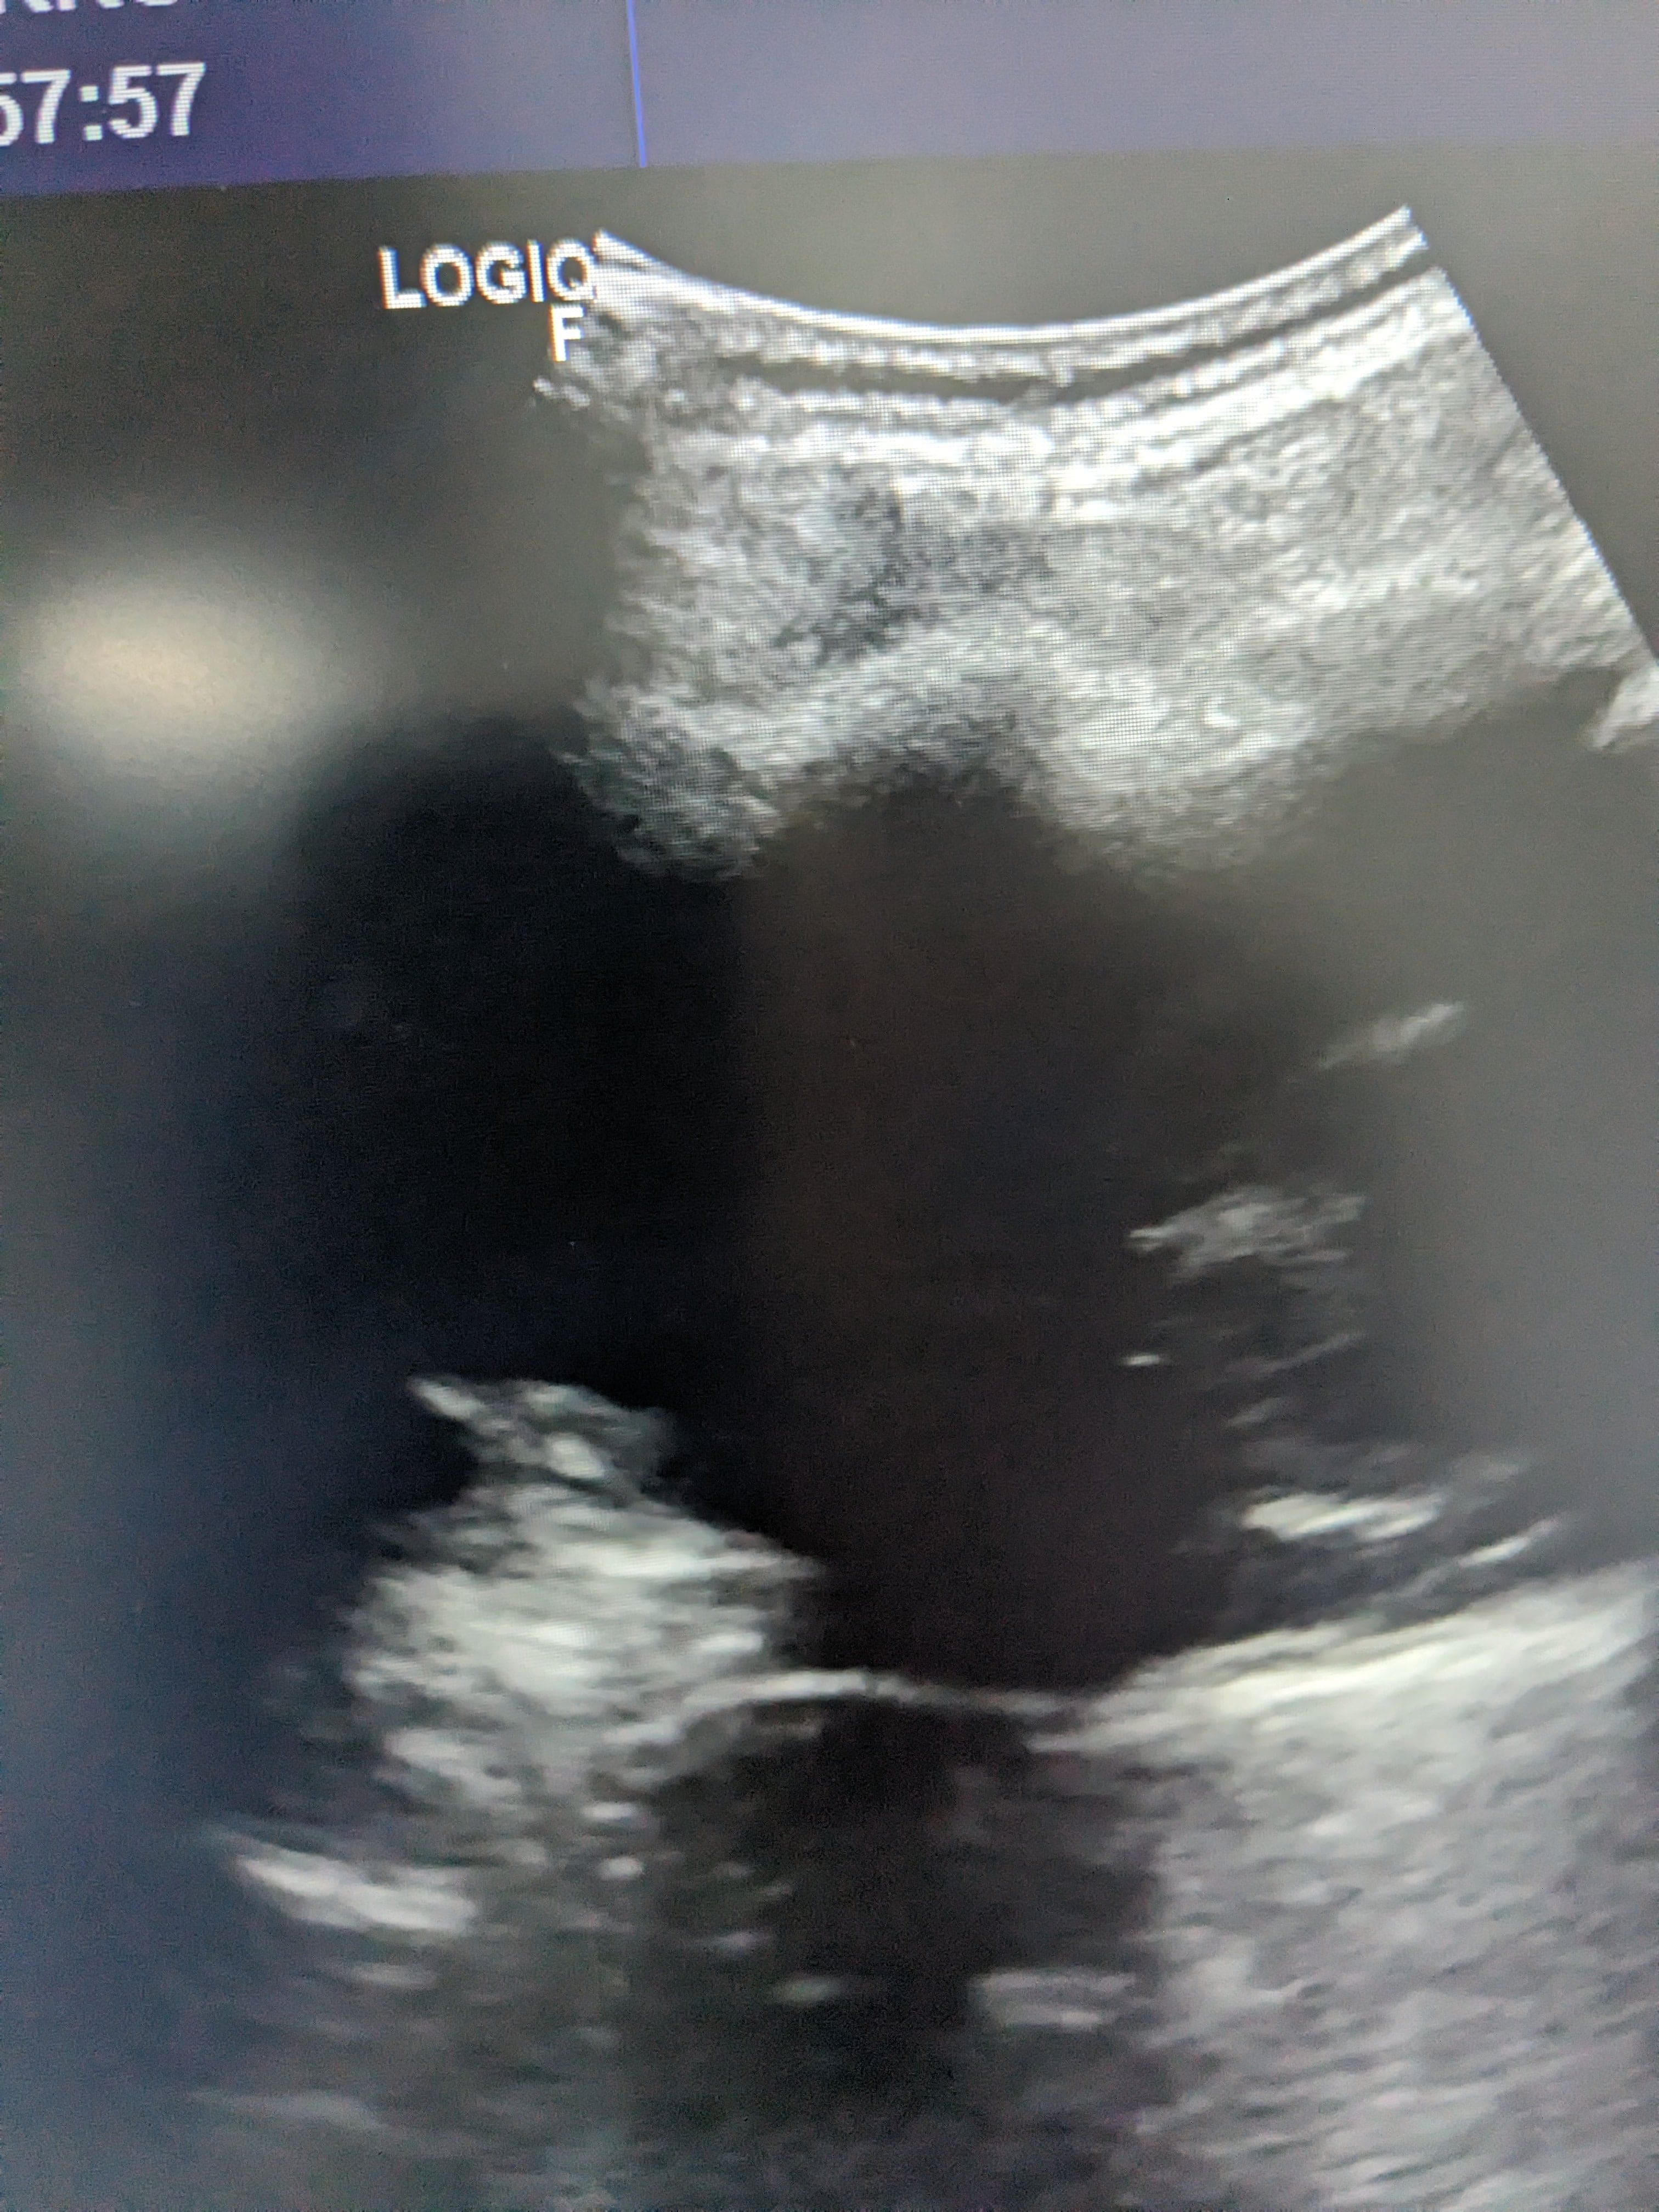

Se hace ecografía clinica en la consulta de atención primaria, observamos derrame pleural en pulmón izquierdo hasta medio campo pulmonar.

Se orienta como derrame pleural de origen desconocido por lo que se deriva a urgnecias del hospital de referencia para valoración de pruebas complementarias y tratamiento.

Rx torax: derrame pleural izquierdo. Sin pinzamiento de seno derecho. Sin infiltrados ni condensaciones.